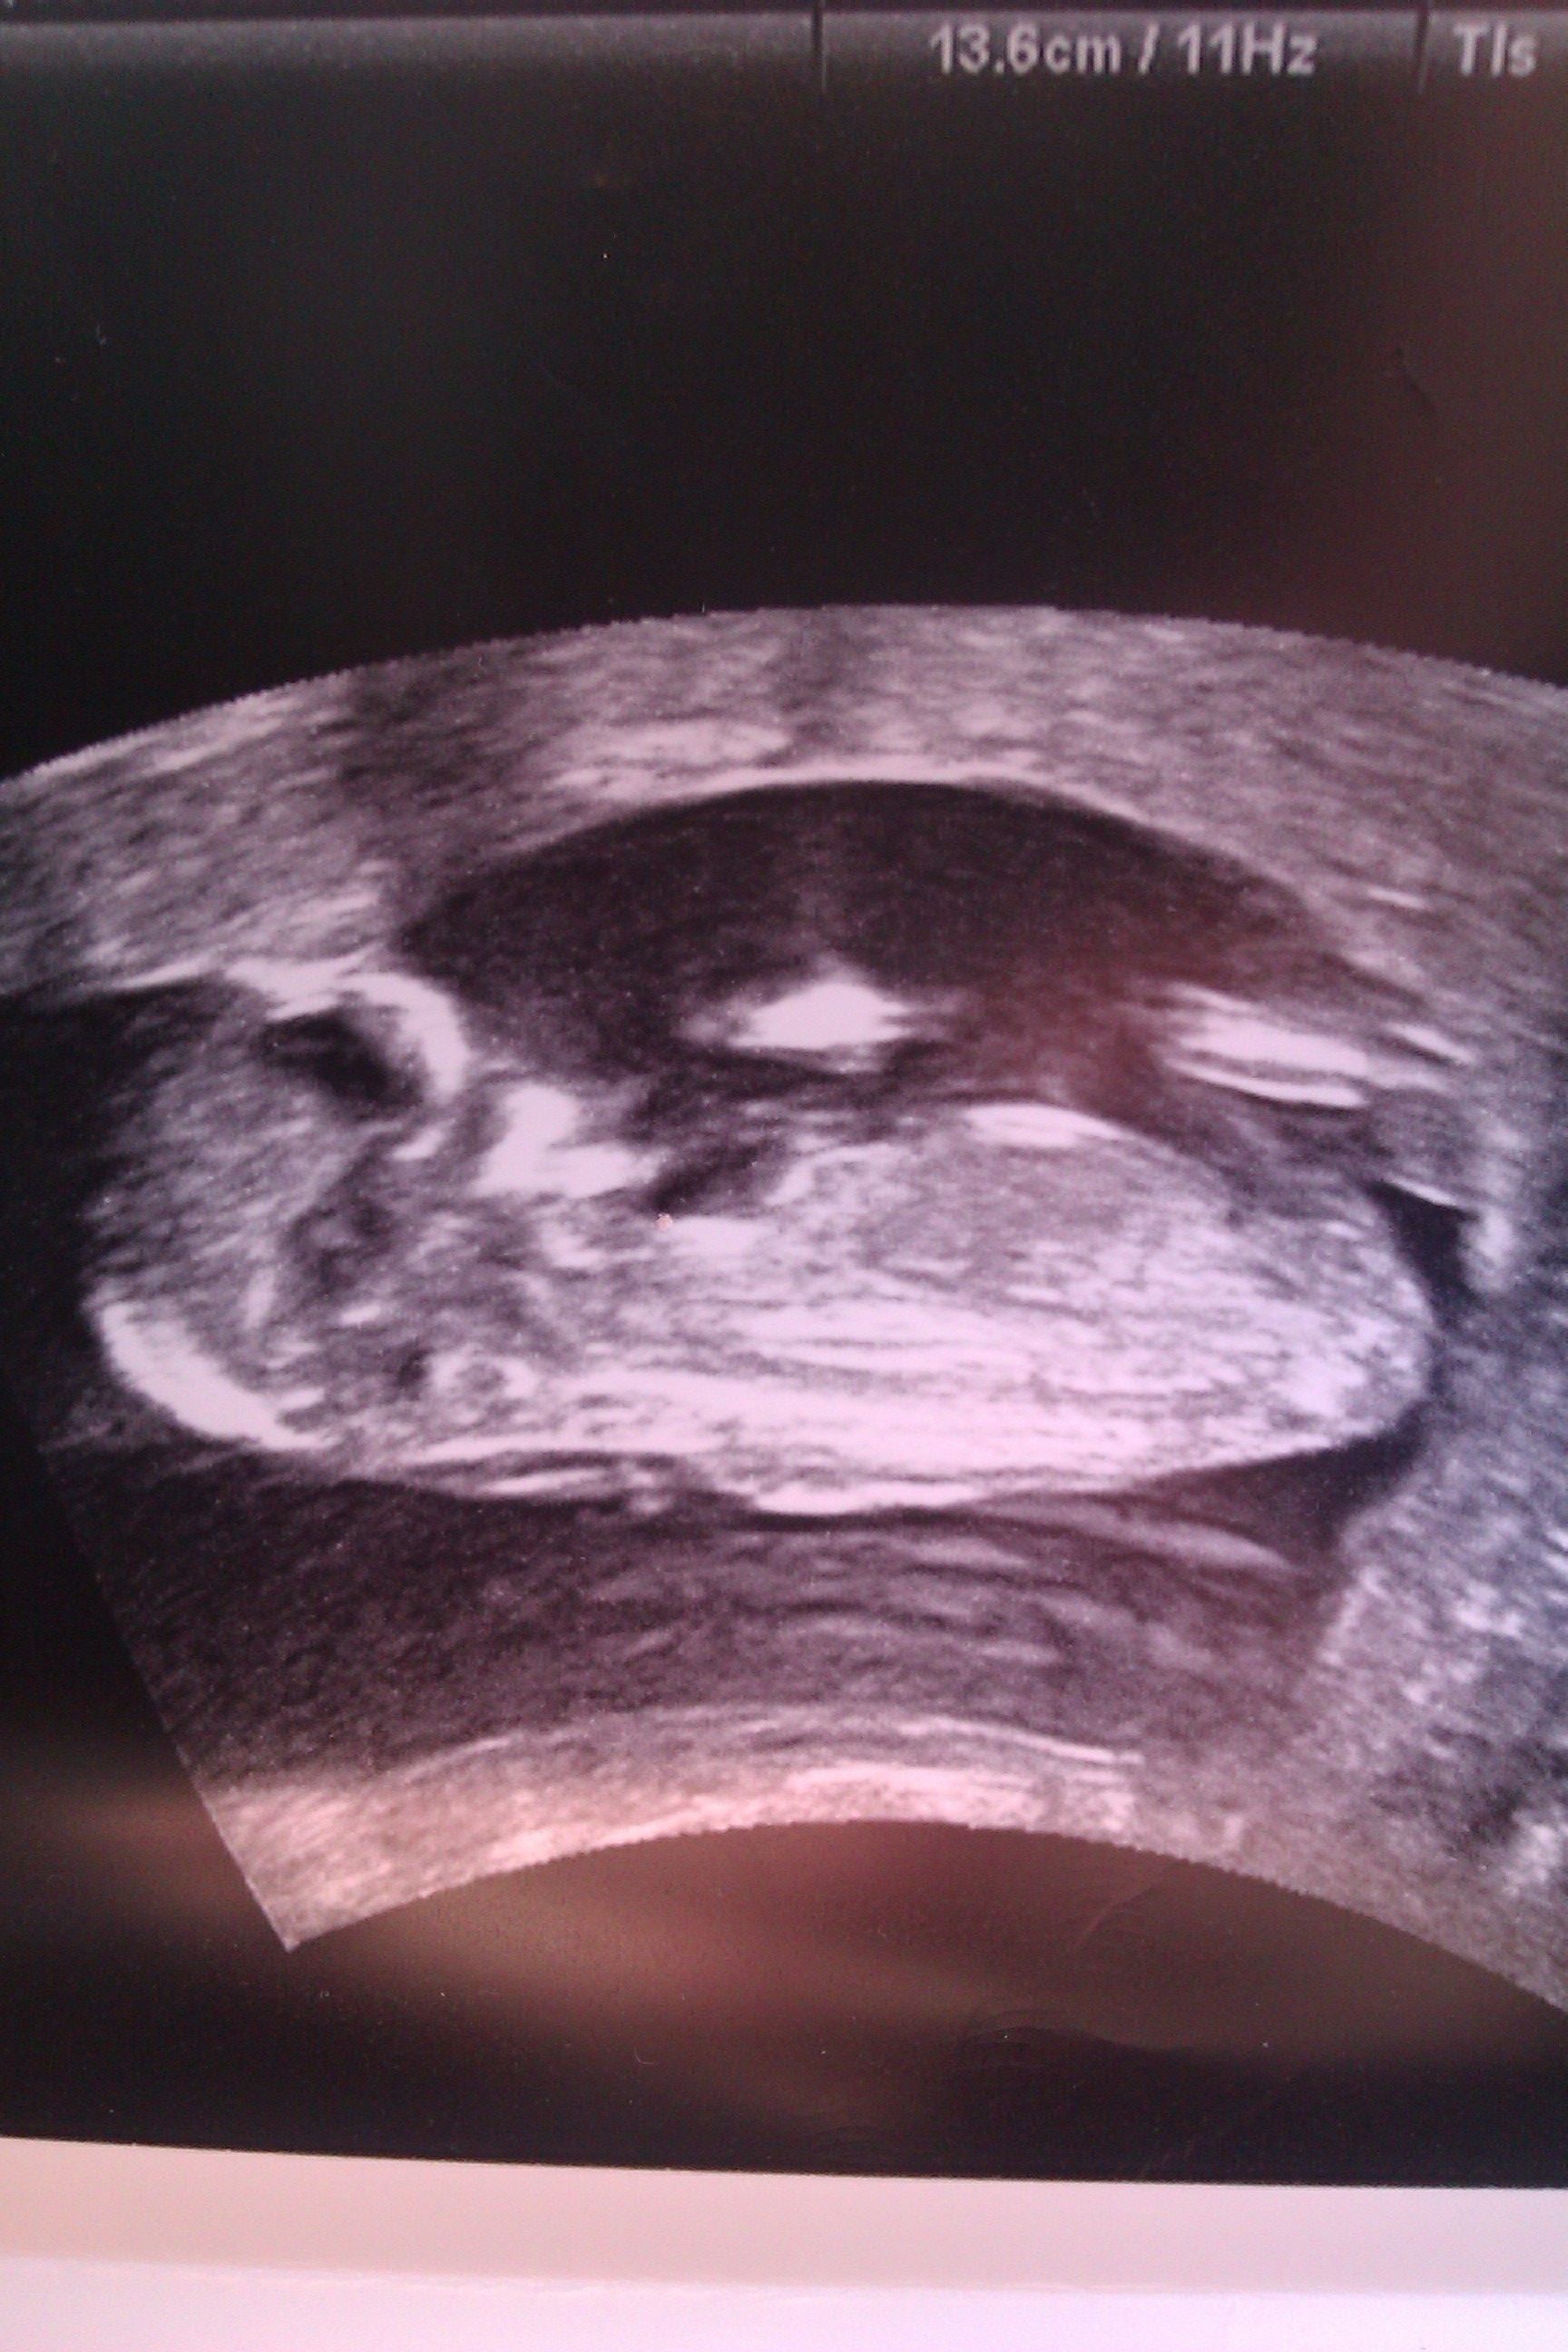

Ultrasound is of baby at 13 weeks exactly would love to know your thoughts. Thanks so much